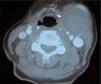

En la exploración vascular, no presentaba soplo cervical y el resto del examen era normal (Fig. 1). En la tomografía computarizada (TC) se visualizó una masa de 4 × 4cm, sin captación de contraste y adyacente a la VYI (Fig. 2). A los pocos días, bajo anestesia general, se resecó un aneurisma trombosado de la VF izquierda con ligadura de los cabos proximal y distal (Fig. 3).